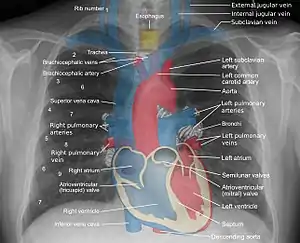

During subclavian vein central line placement, the catheter can be accidentally pushed into the internal jugular vein on the same side instead of the superior vena cava. A chest x-ray is performed after insertion to rule out this possibility.[26] The tip of the catheter can also be misdirected into the contralateral (opposite side) subclavian vein in the neck, rather than into the superior vena cava.

The line is then inserted using the Seldinger technique: a blunt guidewire is passed through the needle, then the needle is removed. A dilating device may be passed over the guidewire to expand the tract. Finally, the central line itself is then passed over the guidewire, which is then removed. All the lumens of the line are aspirated (to ensure that they are all positioned inside the vein) and flushed with either saline or heparin.[1] A chest X-ray may be performed afterwards to confirm that the line is positioned inside the superior vena cava and no pneumothorax was caused inadvertently. On anteroposterior X-rays, a catheter tip between 55 and 29 mm below the level of the carina is regarded as acceptable placement.[37] Electromagnetic tracking can be used to verify tip placement and provide guidance during insertion, obviating the need for the X-ray afterwards.

A central venous catheter secured to the skin with suture Chest x-ray with catheter in the right subclavian vein

Chest x-ray with catheter in the right subclavian vein The outline of superior vena cava on a chest X-ray is labeled at left.

The outline of superior vena cava on a chest X-ray is labeled at left.